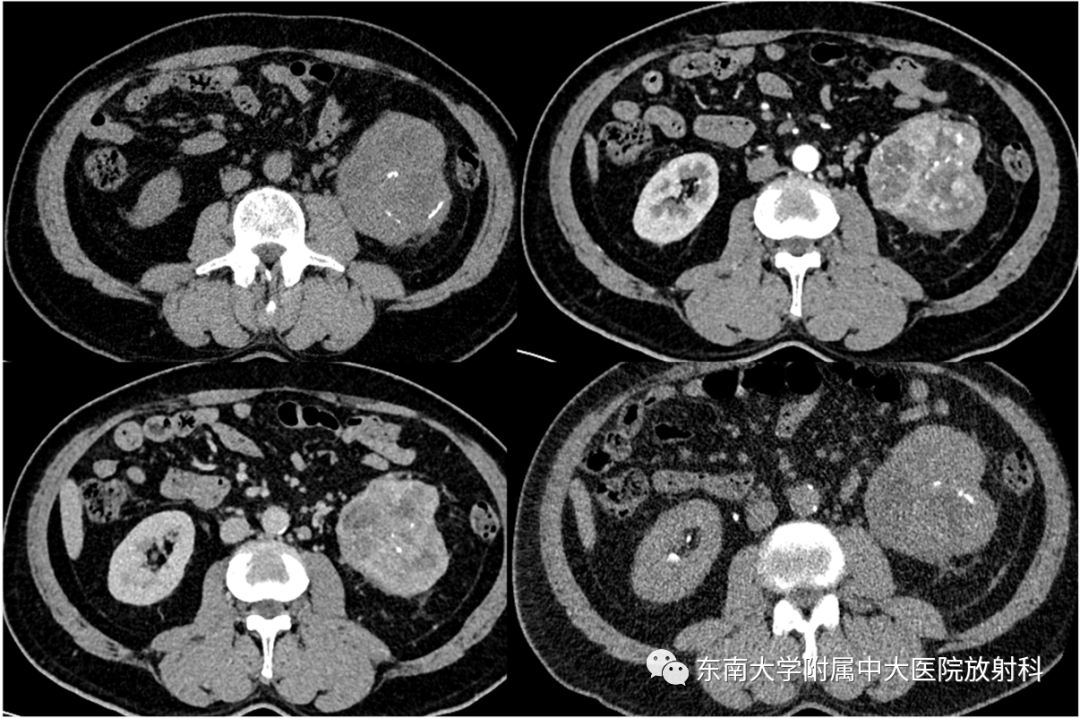

•男,46岁

•主诉:因“咽部不适3月”入院。入院胸部CT提示发现肾脏占位。

•男,54岁

•主诉:因肉眼血尿1月来诊。

•体格检查:肾区叩击痛